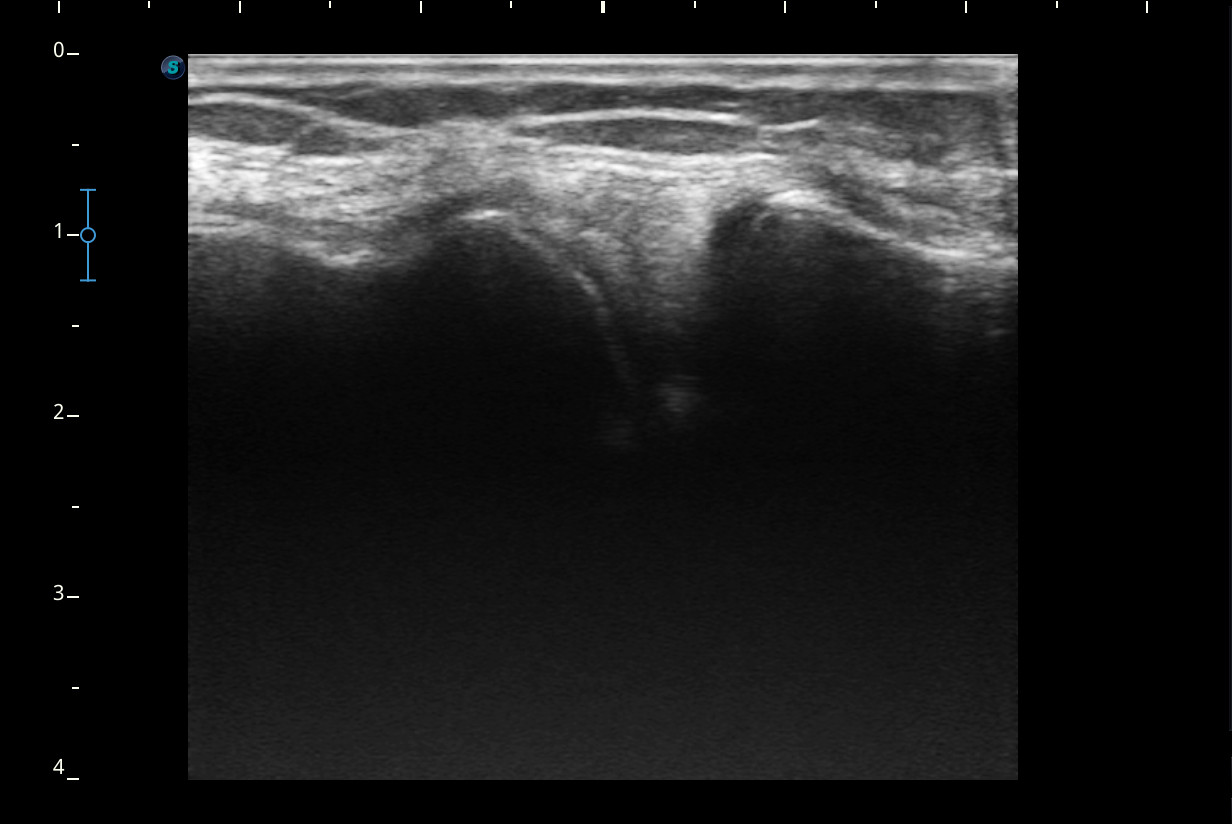

Descripción de los hallazgos ecográficos y las imágenes más relevantes para la resolución del caso

Rodilla sin derrame articular. No se aprecian lesiones en Ligamentos colaterales. Ligamento rotuliano sin hallazgos valorables. Rotura menisco interno y dudosa fisura menisco externo. Tendones rotuliano y cuadricipital normales.